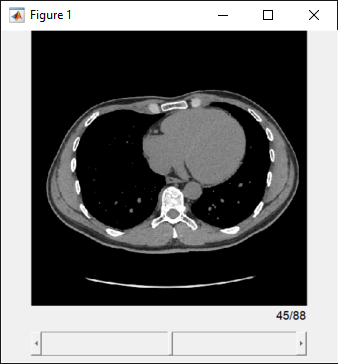

Display 3-D Medical Image Data

3-D medical image data includes volumes from modalities such as computed tomography

(CT), magnetic resonance imaging (MRI), and positron emission tomography (PET). The Medical Image

This table describes the options for displaying 3-D medical image data using Medical Imaging Toolbox. If you do not have Medical Imaging Toolbox installed, see Display and Exploration (Image Processing Toolbox).

| Programmatically display slices along one dimension in a scrollable figure window. | Display the data in the |

| Display Medical Image Volume in Slice Viewer |